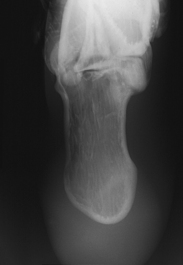

Structures shown: The resulting image shows an axial projection of the calcaneus (Fig. 6-75).

Structures shown: The resulting image shows an axial projection of the calcaneus and the subtalar joint (Fig. 6-78). CT is often used to show this bone (Fig. 6-79).